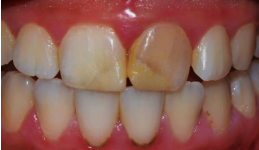

After planning the restorative treatment, a silicone guide was fabricated from the wax-up cast model then intraorally tested (figure 4a). The color selection must be prior to rubber dam isolation because tooth dehydration may mislead the choice of the shade (figure 4b).

Figure 4b. Color selection